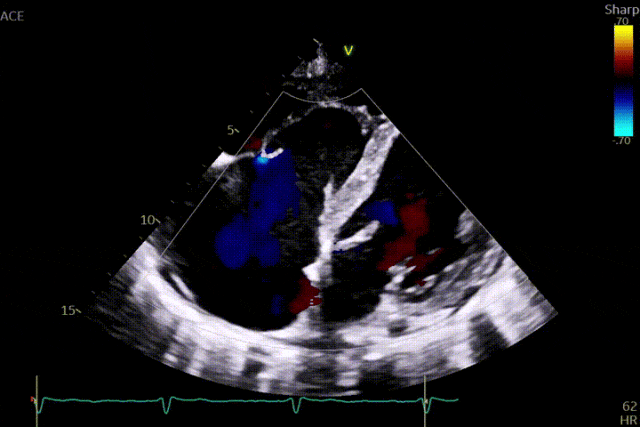

术前超声

术后超声